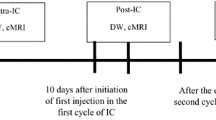

An ROI was manually drawn by a radiologist (specialized in head and neck radiology) to contour the border of NPC on each slice in order to obtain the total tumour volume. The total tumour volume was then calculated on the basis of the segmentation method. Each ROI was contoured on STIR T2W images (Fig. 1a) and co-registered to DW images (Fig. 1b) for analysis using Image J (NIH, Bethesda, MD). Each lesion was measured twice in two separate sessions at 2 weeks apart to ensure reproducibility. The obtained parameters for each lesion were then calculated on a pixel-by-pixel basis and expressed as means of the whole volume analysed.